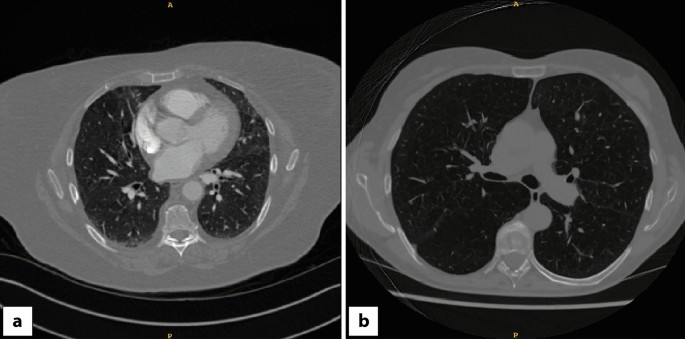

This study was approved by the UK Health Research Authority (HRA) (reference number: 20/HRA/3051), ClinicalTrials.gov identifier: NCT04721444. CT images used for this study were obtained from the National COVID-19 Chest Imaging Database (NCCID)44 (Research Ethics Council (REC) reference number: 20/LO/0688). Patient consent was not required to use this deidentified data as per the respective UK Health Research Authority and UK Research Ethics Council approvals. All methods were performed in accordance with the relevant guidelines and regulations. Informed consent was obtained from the human experts involved in the study. NCCID is a centralized database containing medical images of hospital patients from over 25 centres across the UK. Images were filtered to include only CT images that included the entire thorax. For example, CT coronary angiograms were excluded. 2,078 CT scans were downloaded together with available metadata and manually labelled as either contrast-enhanced or non-contrast by a clinician (Fig. 1).

The examples of the inferred synthetic non-contrast and synthetic contrast CT images predicted from synthetic non-contrast CT are shown in Fig. 5. The absolute intensity difference maps reveal that the trained generators in our framework were able to successfully learn the correct anatomy for contrast removal/transfer despite the heterogeneity in the NCCID dataset. However, in cases with pulmonary angiograms, contrast from hyperdense regions within the chest CT were not fully removed (e.g. Figure 5c). On the other hand, our results demonstrated that the proposed cycle-GAN framework produced photorealistic synthetic contrast CTs from the test dataset, with high visual fidelity closely representing the sharpness and contrast of acquired images. While some differences in contrast intensities were observed on the intensity difference maps (e.g. Fig. 5b–f), the correct structures were identified by the network with no obvious changes to other anatomies on patient scans.

Results of cycle-GAN training on eight example test cases (a–h) for contrast to non-contrast CT synthesis. The absolute intensity difference maps show the scaled intensity differences between normalized acquired contrast/synthetic non-contrast and synthetic contrast/acquired contrast CTs (intensity range: −400, 400HU; normalized intensity range: −4.0, 4.0). The framework successfully removed and predicted contrast on test chest CTs (e.g. a,d,h). Contrast regions within synthetic contrast images were mainly removed from pulmonary arteries, with some cases showing intensity differences due to variable contrast agent injection timepoints (e.g. b,e,f,g). The white arrow represents structures where hypo-intensity remains on chest CTs after synthesis (e.g. c).